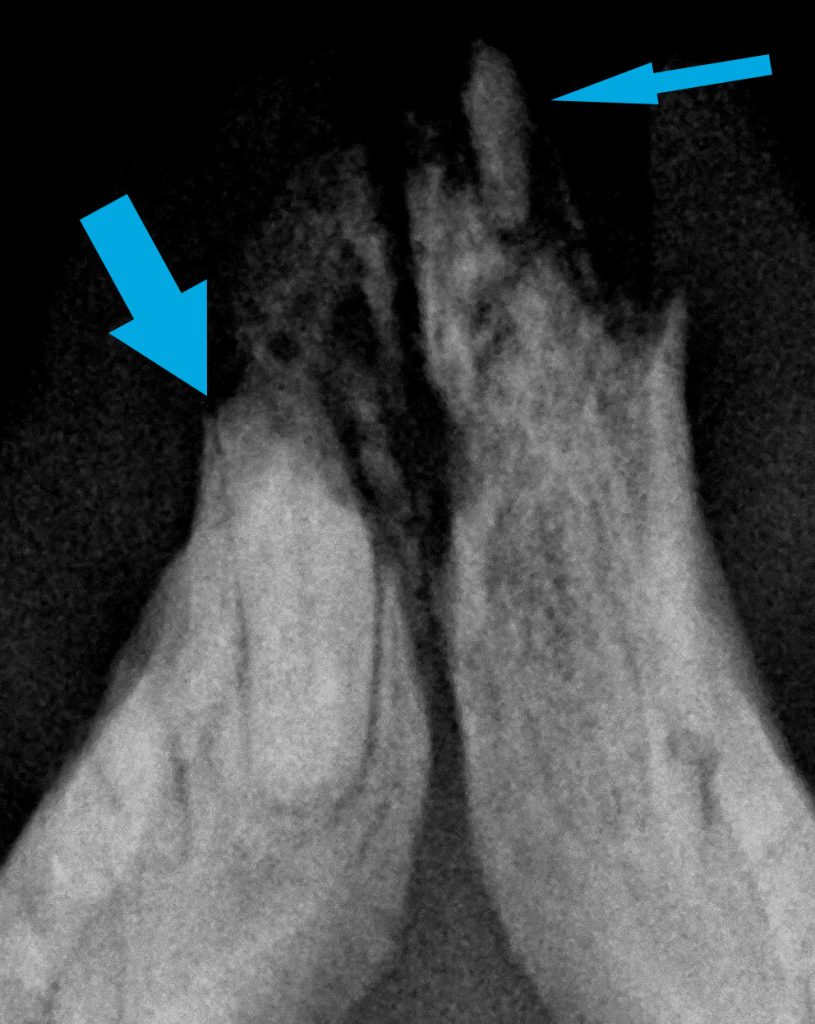

ESTUDIO RADIOLÓGICO DENTAL

El estudio radiológico dental correspondiente desveló la presencia de restos radiculares de los dientes 207 302, 308, 404, 408, 409 (incisivo, premolares y colmillo).

Se llevó a cabo la exondocia del incisivo y los otros 7 restos radiculares encontrados mediante cirugía de flap gingival y fresado del hueso alveolar de cada diente.

-Al ser la GECF una enfermedad idiopática de origen inmunomediado es imprescindible que no queden restos radiculares en la cirugía de exodoncias para evitar así el estímulo antigénico que mantenga la inflamación y el dolor en el paciente.

-Dado el escaso tamaño de los dientes del gato, sin la técnica ni el equipamiento adecuado, es relativamente sencillo dejar algún resto radicular (en ocasiones de forma desapercibida). El fresado «a ciegas» de un posible resto radicular, además de que está contraindicado por sus posibles complicaciones asociadas, no soluciona el problema de que queden restos radiculares.